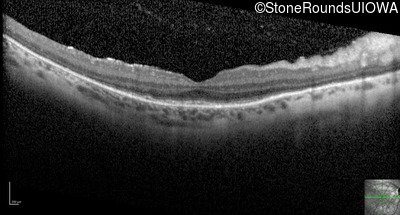

Optical Coherence Tomography - Left - 20/40 -2

Exemplar / OCT Stack